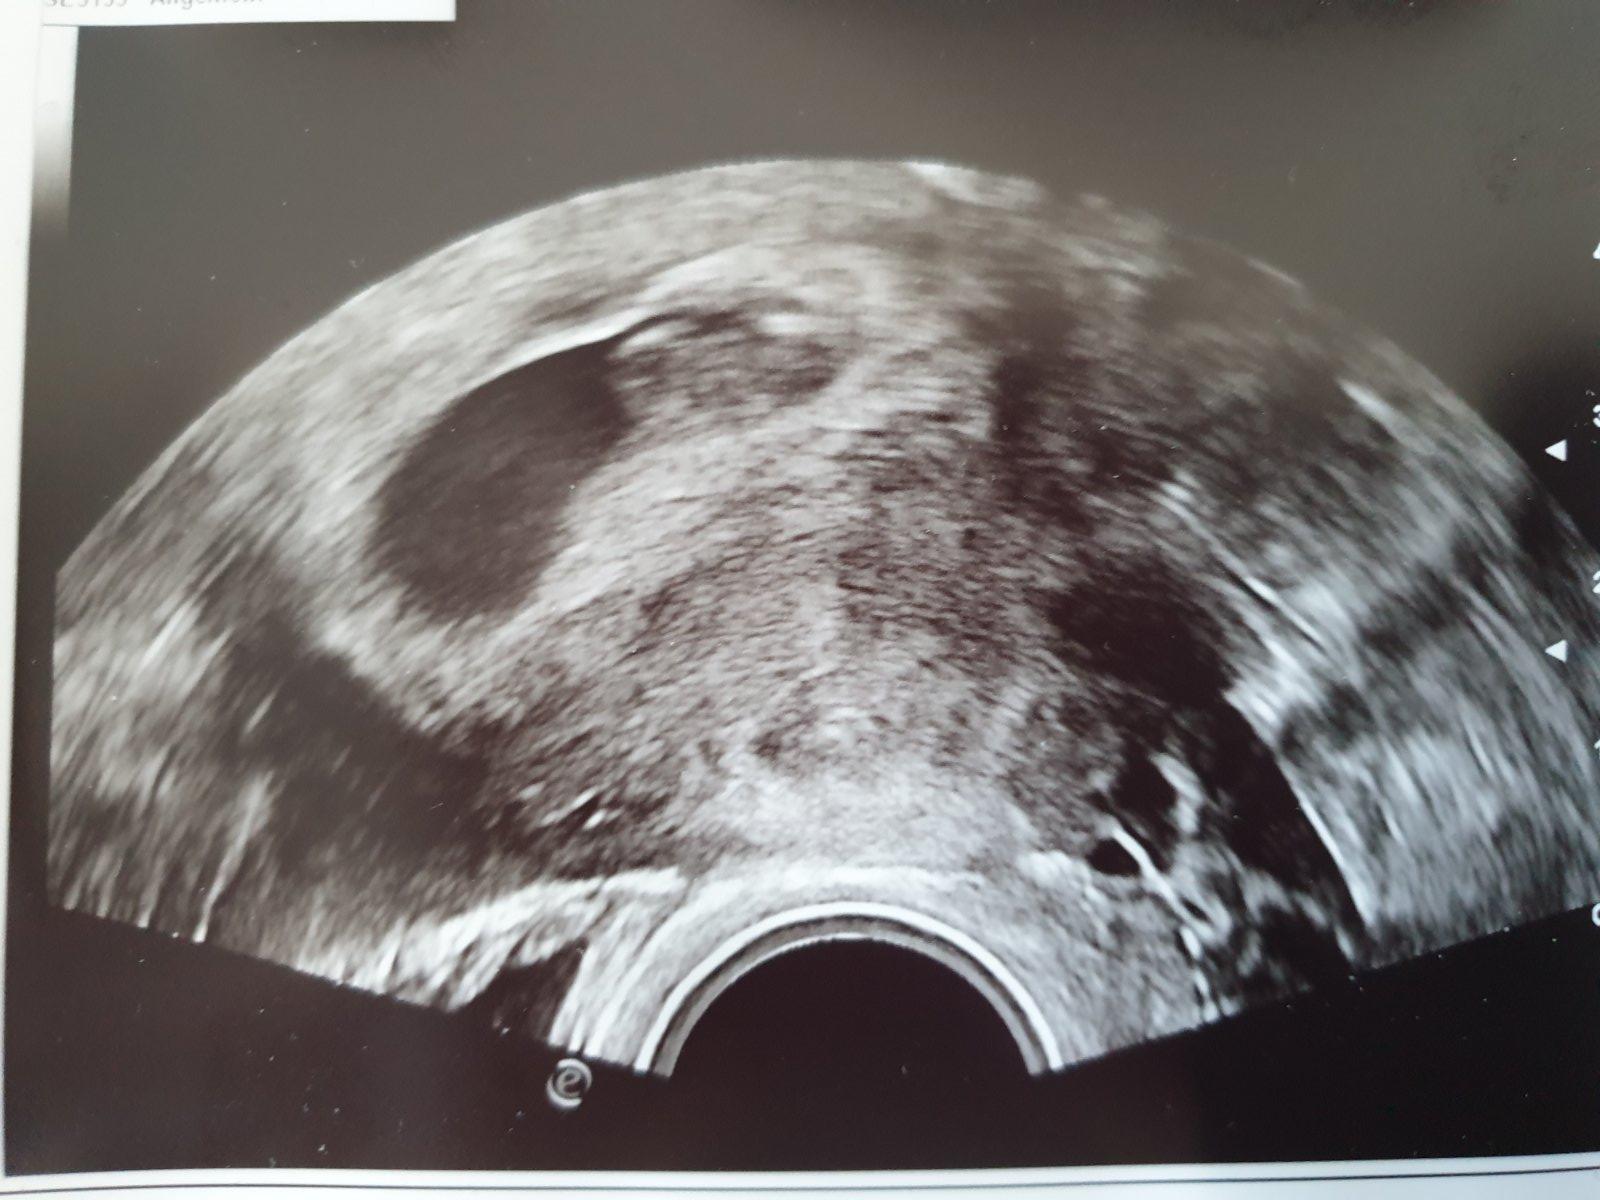

@butterfly333 @kakatulik dakujem 😍 az mi slzy tiekli ked som videla to blikajuce svetielko, srdiečko. Moc drobca nechcela ultrazvukom vyrušovať, ani nešla do hlbky, ze je velmi malé ešte a ze ho nebude rušiť 😍